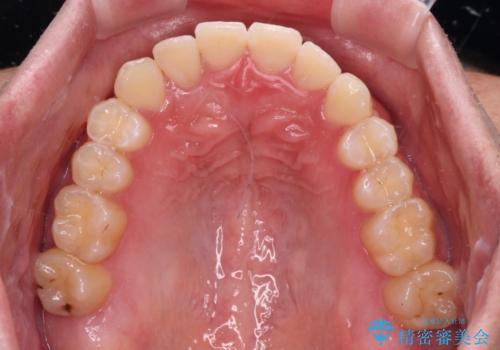

- 前歯のクロスバイトを気にして来院された患者様です。

骨格的には問題がなかったため、インビザラインを用いて咬み合わせを改善していくこととしました。

インビザライン特有の、奥歯の咬み合わせの問題もなく、しっかりと歯列を改善することができました。

舌側転位している上顎側切歯(内側に引っ込んでいる真ん中から2番目の歯)は、インビザラインが最も移動を苦手とする歯であり、これ以上の改善を望まれる場合にはワイヤー矯正、あるいはワイヤー矯正の併用をお勧めいたします。